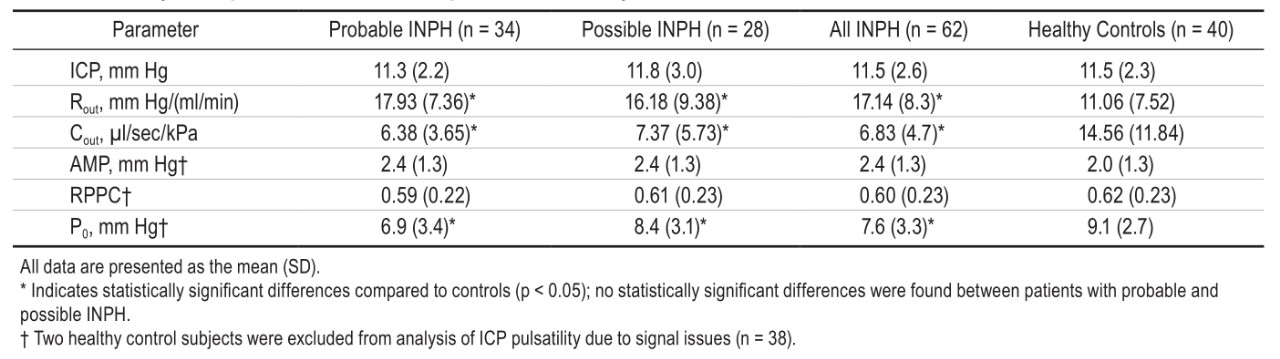

颅内压(ICP)、流出阻力(Rout)和心脏相关ICP搏动(AMPs)幅值是描述CSF水动力学系统的既定参数。人们通常认为这些参数(但未证实)在特发性常压性脑积水(INPH)中受到影响。作者在本研究中,比较了INPH患者和健康志愿者之间的CSF流体动力学特征差异。本次研究包含了62例INPH患者(平均年龄74岁)和40名健康志愿者(平均年龄70岁)。由两位神经学医生通过评估患者的病史、神经学状态和MRI结果后独立作出诊断。通过腰椎穿刺进行CSF动态研究。在本次研究中,神经科医生对ICP和其他CSF动态变量在诊断过程中采取盲法,并且不作为INPH的诊断依据。结果如下:尽管相当数量的INPH受试者有正常的Rout值,但INPH组Rout值明显高于正常对照组(ROUT17.1vs11.1;p<0.001)。INPH患者和对照组在ICP方面没有差异(平均11.5mmHg)。静息压力下,INPH组AMP有升高的趋势(2.4vs2.0mmHg;p=0.109)。AMP和ICP之间的具有相同的斜率,但INPH的曲线显著左移(P0降低[p<0.05];即相同ICP的AMP较高)。作者得出结论,本研究证实INPH的脑脊液动力学与健康志愿者的脑脊液动力学特征有显著差异,因此INPH应被认为是一种颅内流体动力学发生病理生理学改变的疾病。

图:特发性常压性脑积水患者与健康志愿者在颅内压(ICP)、流出阻力(Rout)和心脏相关ICP搏动(AMPs)幅值等脑脊液动力学方面的差异比较。